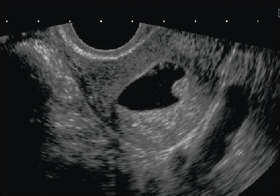

図1 妊娠10週2日,経膣4D動画像

産婦人科医院のホームページ宣伝には大いに使える。